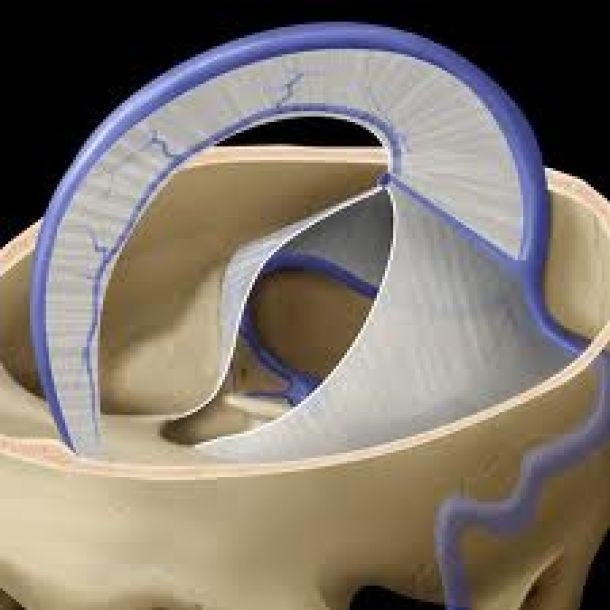

ΣΥΣΤΗΜΑ ΜΕΜΒΡΑΝΩΝ ΚΡΑΝΙΟΥ